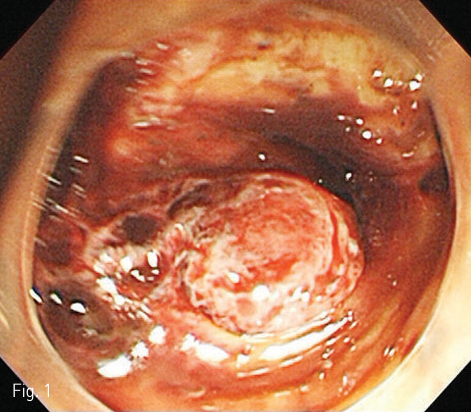

우측 대퇴동맥을 Seldinger method로 천자한 뒤, 6Fr sheath (Accu-sheath, SungWon Medical, Cheongju, Korea)를 삽입하였다. 0.035”유도철선 (Radifocus guidewire M, Terumo corp., Tokyo, Japan)과 Yashiro catheter (RHR, Cook Medical, USA)를 이용하여 복강동맥을 선택하여 혈관조영술을 실시하였다. 복강동맥조영술에서 고유간동맥의 불규칙한 혈관내경 감소와 낭성 돌출을 보이는 혈관병변이 관찰되어 내시경에서 보인 가성동맥류로 판단하였다. (Fig. 2). 이 병변에 스텐트 그라프트를 설치하기 위해 8Fr angio sheath(Accu-sheath, SungWon Medical, Cheongju, Korea)로 교체한 뒤, 같은 방법으로 Yashiro catheter를 고유간동맥까지 진입시킨 상태에서 0.035” 유도철선 (Radifocus Guidewire M, Stiff type, Terumo corp., Tokyo, Japan)을 우간동맥까지 조심스럽게 진입시켜두고, 병변부에 말초혈관용 스텐트 크라프트 (6mm x 4cm, Hercules Vascular Stent-graft, S&G Biotech, Seongnam, Korea)를 설치하였다. 설치 직후 병변부 주변으로 일시적인 혈관연축이 관찰되었으나, 전반적인 관류 상태는 양호하였으며, 혈관병변들이 호전된 것을 확인할 수 있었다(Fig. 3).

Fig 2

Celiac angiography shows vascular irregularity and vasospasm of the hepatic artery proper. Also, there is a small saccular outpouching lesion at stump site of the gastroduodenal artery, and we can presume the location of saccular pseudoaneurysm at duodenal bulb by the duodenal vascular staining.